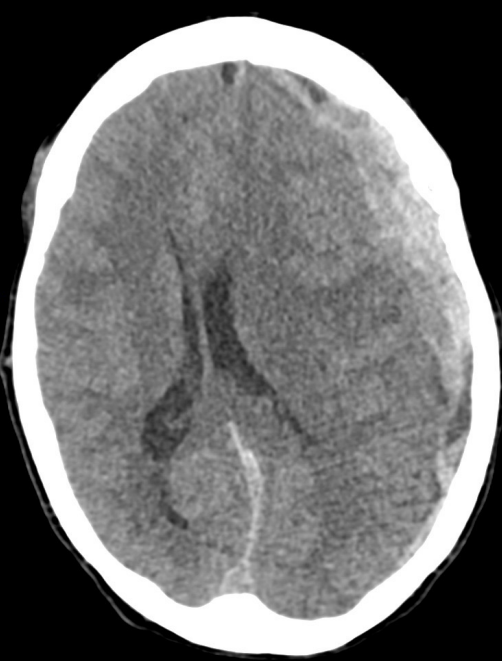

Name the pathology

Intracerebral haemorrhage (bleed)